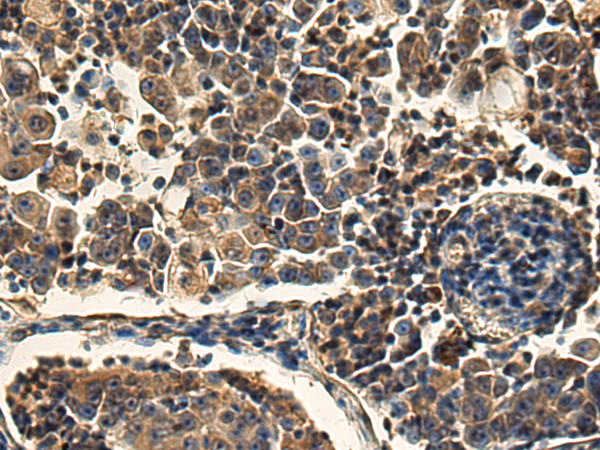

分类: 科研抗体货号: P02094别名: EMC5; TMEM32应用: WB,IHC反应种属: Human, Mouse, Rat